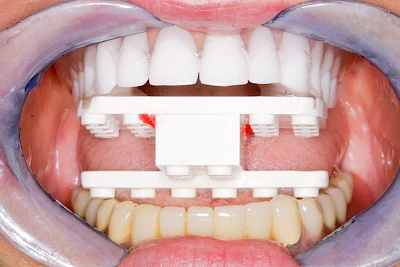

Implantate: Kronen & Brücken

Fehlen einzelne Zähne und die Nachbarzähne sind unbeschadet oder gut zahnärztlich versorgt, werden immer häufiger Implantate gewählt, um die Lücken zu schließen. Auch bei größeren oder verteilten Lücken, wenn keine herausnehmbare Prothese gewünscht ist, werden Implantate für Kronen- bzw. Brückenversorgungen gesetzt. In Einzelfällen entscheiden sich sogar zahnlose Patienten für eine festsitzende Versorgung auf Implantaten.

Varianten zur Verankerung von festsitzendem Zahnersatz auf Implantaten